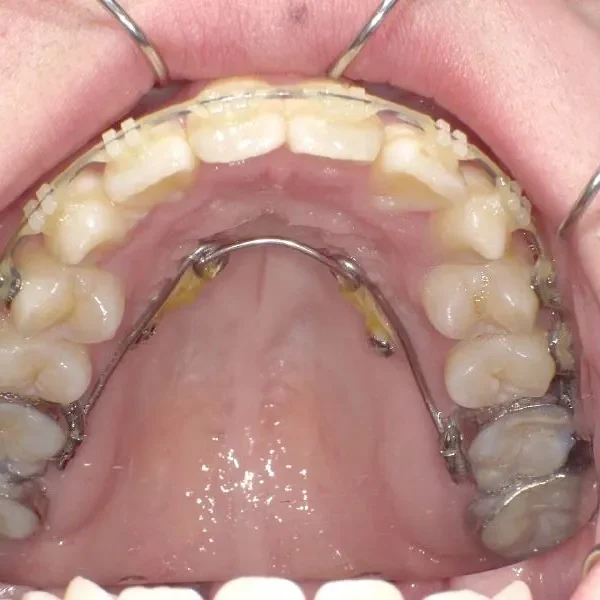

【大人の矯正】叢生・八重歯・交叉咬合・非抜歯症例・19歳女性【R.T様】

初診時年齢 19~29歳 (女性) 主訴 ガタガタ・交叉咬合が気になる

診断名 叢生・交叉咬合 装置名

矯正用アンカースクリュー4本・マルチブラケット矯正装置

抜歯の有無 非抜歯 治療期間・通院回数 3年 1ヶ月 / 42回

ガタガタ・八重歯を主訴に来院された患者様です。

頬杖をする癖がおありでした。

治療回数42回、3年1ヶ月の治療期間で矯正治療を終了しました。

主訴が改善され、ご満足頂きました。

正中のすき間については保定期間にも調整しています。